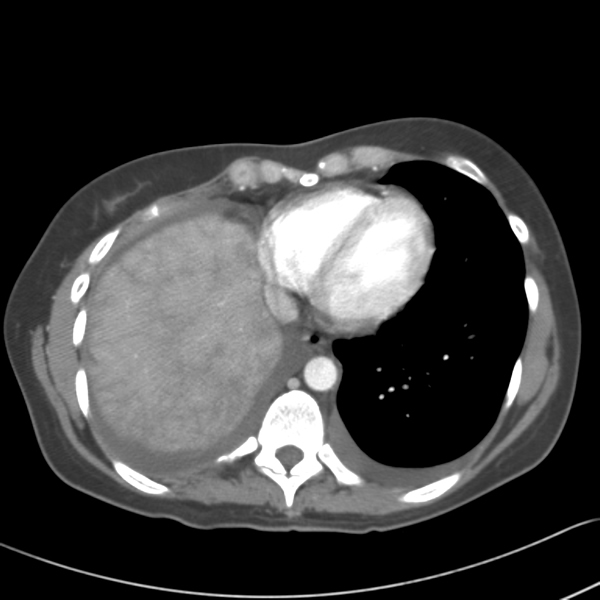

By 29 weeks of gestation, she was increasingly symptomatic with exertion and was found to have a slight reduction in her PFTs to an FVC of 2.07 (51% of predicted) and a FEV1 of 1.65 (49% of predicted). Non-operative management was again recommended and at 38 weeks gestation she delivered a healthy baby. However, her hospitalization was complicated by fever and elevated liver enzymes. An abdomino-pelvic CT revealed an enlarged and heterogeneous liver and loculated R hydropneumothorax. At 4 months follow-up, she was found to have persistently elevated liver function tests. A new CT scan revealed passive congestion in the right lobe and a three cm hypervascular lesion in the left lobe (Figure 2). Further evaluation with MRI revealed passive congestion of the right lobe of the liver with herniation into the thoracic cavity resulting in right hepatic vein compression at its junction with the inferior vena cava (Figure 3). Multiple additional lesions were felt to be consistent with fibronodular hyperplasia.

Consultation with general and thoracic surgery services agreed that operative correction was required due to progressive symptoms and partial hepatic vein obstruction. VATS revealed that the right lobe of the liver was entirely in the right chest, the margins of the diaphragmatic defect could not be seen, and there was no hernia sac (Figure 4). The right lung was trapped and there were multiple adhesions present.